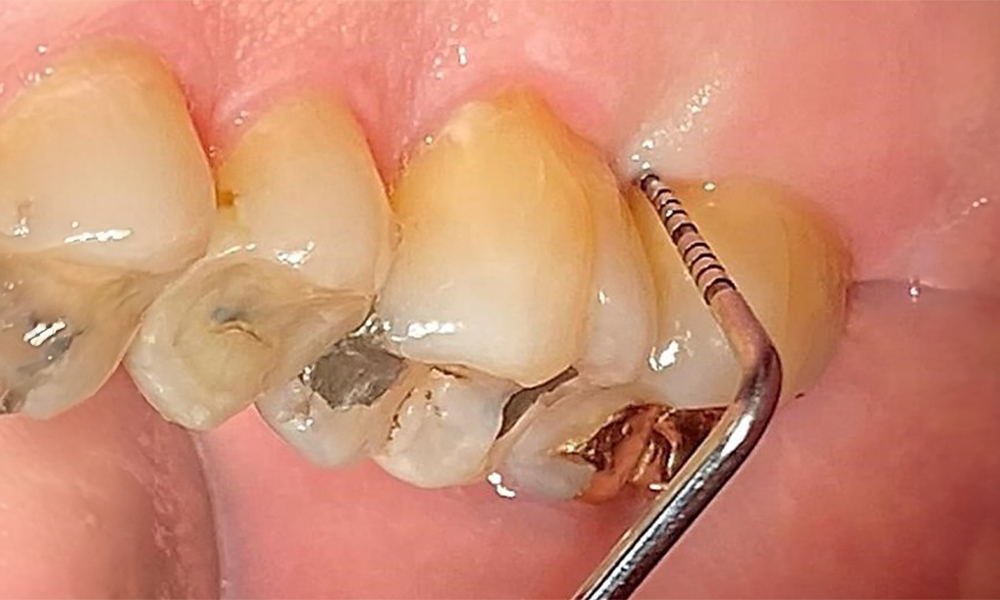

Dental findings

The patient has a full dentition with 28 teeth, which includes amalgam and composite fillings in the molar and premolar regions. There is a visible clinical marginal gap present on tooth 14. Tooth 27 has an adequate gold inlay. There are also generalized attritions and abrasions. (Fig. 2, Fig. 3, Fig. 4, Fig. 5, Fig. 6)

Periodontal findings

The patient has stage II, grade B periodontitis (5). At 1 to 3 mm, the clinical probing depths were within the physiological range. Localized probing depths of 5 mm were observed on the mesiopalatal aspects on both 17 and 27. There are generalized recessions of 1–3 mm with partial loss of the interdental papillae (Fig. 2, Fig. 3, Fig. 4)